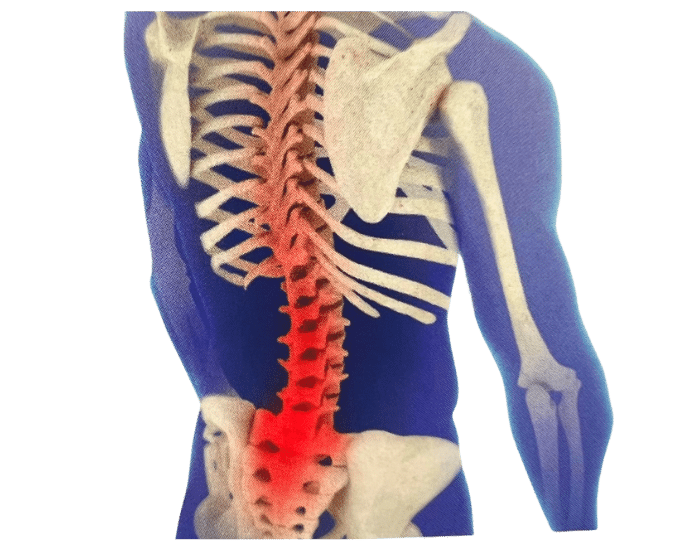

There are numerous reasons why you might need Custom Foot Orthotics. If you have pain in your foot, heel, knee or hip, have high arches or flat feet; or just being regularly on your feet and are getting any aches or pains in the feet or legs, or suffering from general foot pain while walking, running, playing sports or even at rest you qualify for Custom Foot Orthotics.